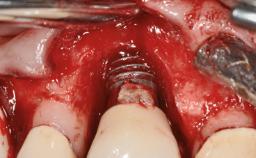

Peripheral Giant-cell Granuloma Associated with Peri-implant Tissues